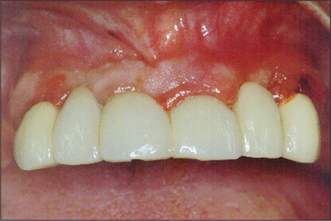

Hemisection and root amputation

These procedures may be indicated if an adequately root-filled molar has a periodontal furcation involvement, a vertical root fracture, or a single root which is not otherwise amenable to endodontics. The lesion is managed by removing the involved root (and the overlying crown), and then sealing and preserving the remaining root and crown (Figs 6.17, 6.18). A full periodontal assessment is necessary before planning these procedures.

Fig. 6.17 Hemisection for vertical fracture.

Fig. 6.18 Root resection followed by sealing of a tooth.